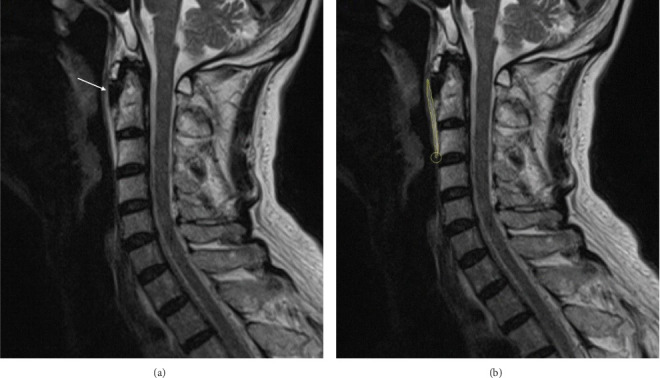

Objectives: Longus colli tendinitis (LCT) is a rare, self-limiting disease primarily characterized by neck pain. This study is to investigate and analyze the imaging and clinical features of LCT and to develop a predictive model for pain risk in LCT based on these features. Methods: This study included 35 patients with LCT enrolled between January 2017 and December 2024. Radiological features, laboratory indicators, and clinical profiles were systematically analyzed. We stratified LCT patients into high-risk (n = 20) and low-risk (n = 15) groups based on pain intensity and duration. Nomograms were developed using logistic regression models, with feature selection performed via the least absolute shrinkage and selection operator method. Model performance was evaluated through discrimination (Harrell's C-index) and calibration (calibration plots), with internal validation conducted via bootstrapping. A clinical impact curve was used to assess the model's clinical usefulness. Results: MRI features of LCT included average lesion width of 6.13 mm, length of 64.00 mm, circumference of 134.52 mm, and area of 230.64 mm2. Clinically, LCT patients exhibited elevated white blood cell counts, neutrophil counts, hsCRP levels, and IL-6 levels. Feature selection revealed that the lesion area could predict pain risk in LCT patients, which was used to construct a predictive model. The model demonstrated a C-index of 0.93 (95% CI 0.84-0.99). Internal validation confirmed the model's robust performance, with a C-index of 0.93 (95% CI 0.83-0.99). Conclusion: LCT possesses distinct imaging and clinical features. Utilizing these features enables effective prediction of pain risk, thereby assisting clinical decision-making.